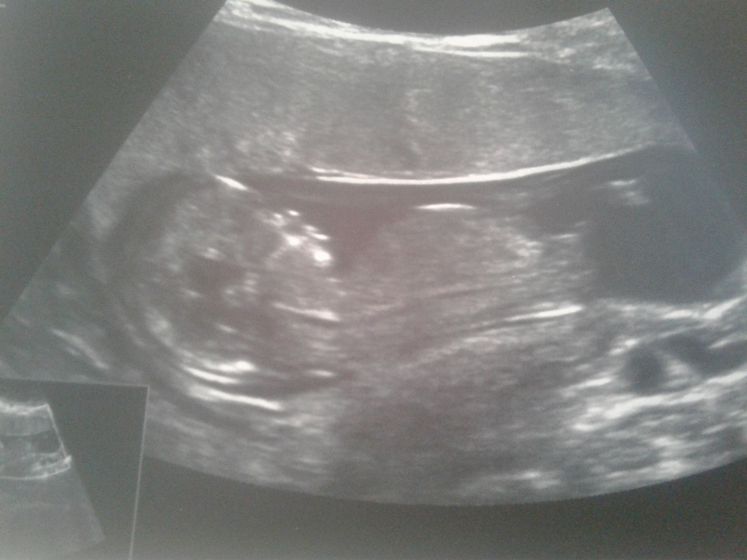

Для всех кто поддержал! Наш первый скрининг прошел удачно. Врач — Ярыгина Тамара Александровна — просто чудо! Все слава Богу в норме. Растет, развивается, все ростовые нормы догнал. Рост у него 67,5 мм, твп 1,6, аккуратненький носик на месте. Подвижный очень, будет братику жару давать. И у нас второй сыночек скорее всего. Наш маленький Сереженька! Люблю всей душой. Девочки, милые, спасибо за поддержку, за теплые слова! Мне после замершей было безумно тревожно! Всех обнимаю! Всем добра!

Плацента толщиной 1,4, сказала хорошая ровная, по задней стенке. Без включений.

Предлежит не полностью, краем. Но врач сказала что на этом сроке у 99% предлежание. Это абсолютно непоказательно по ее мнению. Она врач-эксперт из нии акушерства и гинекологии им кулакова. Думаю можно верить)